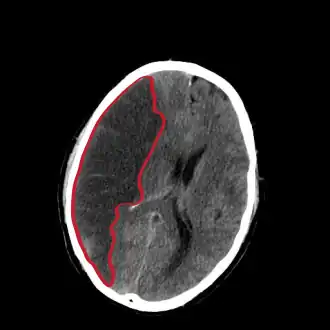

Компьютерная томограмма головного мозга, демонстрирующая инфаркт в правом полушарии головного мозга (зона инфаркта обведена красным.)